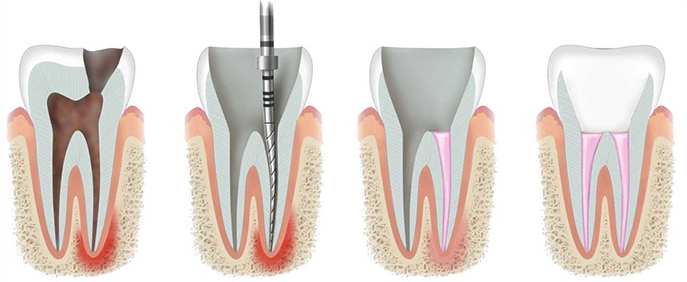

Leczenie endodontyczne krok po kroku

Leczenie kanałowe pod mikroskopem to precyzyjny, wieloetapowy zabieg, którego celem jest usunięcie infekcji i uratowanie naturalnego zęba. Poniżej przedstawiamy, jak wygląda krok po kroku nowoczesne leczenie endodontyczne w naszym gabinecie Prodental  Tarchomin / Nowodwory.

To najważniejszy etap leczenia endodontycznego. Celem tego etapu jest usunięcie bakterii, resztek miazgi i toksyn z całego systemu kanałowego – również z kanałów bocznych i dodatkowych. Obejmuje:

• opracowanie kanałów elastycznymi narzędziami niklowo-tytanowymi

Po dokładnym oczyszczeniu kanały są szczelnie wypełniane materiałem biokompdtybilnym. Prawidłowe wypełnienie zapobiega ponownej infekcji i stanowi warunek długoterminowego powodzenia leczenia.

Ostatnim i niezwykle ważnym etapem jest odbudowa korony zęba. Prawidłowa odbudowa znacząco zmniejsza ryzyko złamania zęba po leczeniu kanałowym. W zależności od stopnia zniszczenia tkanek stosujemy:

Etapy leczenia endodontycznego